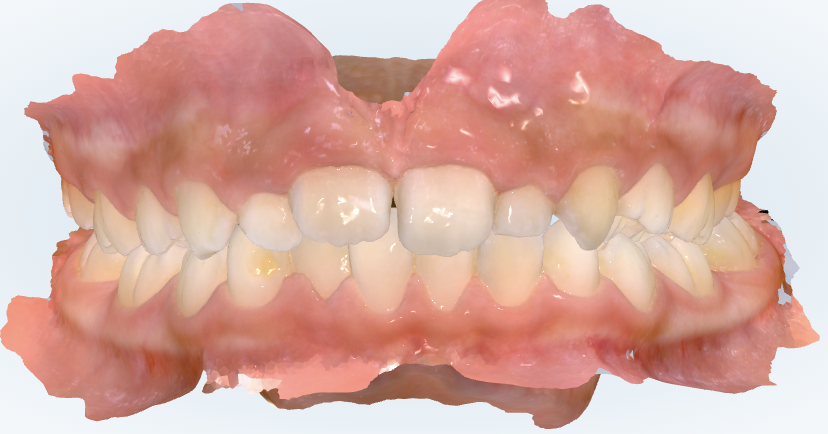

初診時の画像診断

永久歯への生え替わりが遅いです。

下あごの噛み合わせが左にずれて噛むことが習慣化しています。

スキャンで見ると、確かに上も下もガタガタがあります。ただ、ガタガタが重度というわけではありません。

一方で、奥歯の噛み合わせを左右で見ると、右と左でズレ方が違うのが気になります。

右側はそこまで悪くないんですが、反対側を見るとズレが少し大きいです。

これは歯だけの問題というより、下顎が少し左右にずれて噛んでいるつまり顎が偏位している可能性が高いです。

あと、噛み合わせが少し深めです。極端に深くて歯ぐきを傷つけているような状況ではないですが、成長を利用してこれ以上深くならないようにコントロールするのは大事なポイントです。